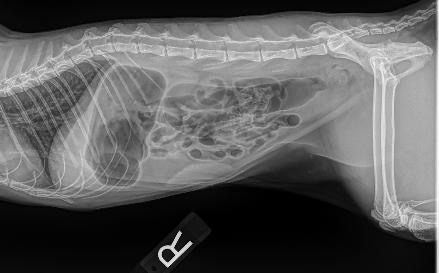

As many know, my pets are like my children. Zoey, my Sphynx cat, may have a small bowel obstruction and might require surgery. She began to not eat for a day and a half, also showing signs of nausea by gagging. I always take every precaution that there is. I have elevated bowls for all my cats. Zoey gets high-quality food. They get probiotics for their teeth. But in this case, I don’t know why this happened. Zoey is required to stay overnight in the ER for fluids and 12 hours of observation. Please, anything helps. I love her so much and I wouldn’t want to lose her.